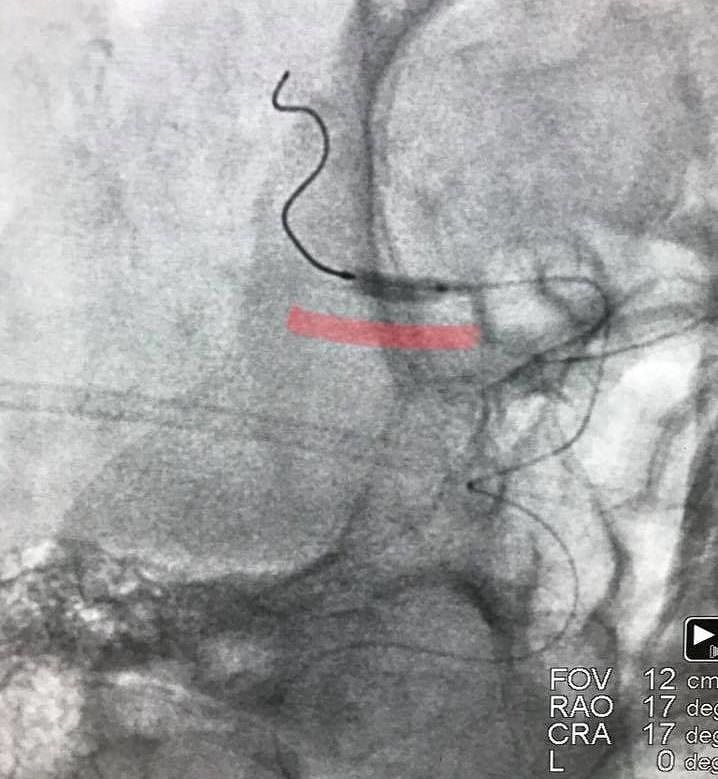

AGRIGENTO. L’esecuzione di un delicatissimo ed innovativo intervento chirurgico presso il reparto di emodinamica dell’ospedale “San Giovanni di Dio” di Agrigento apre a singolari scenari nel trattamento dell’ictus cerebrale. Attraverso un’angioplastica percutanea è stata salvata la vita ad un paziente in condizioni critiche ed il risultato ottenuto consente di gettare nuove luci nel trattamento della patologia.